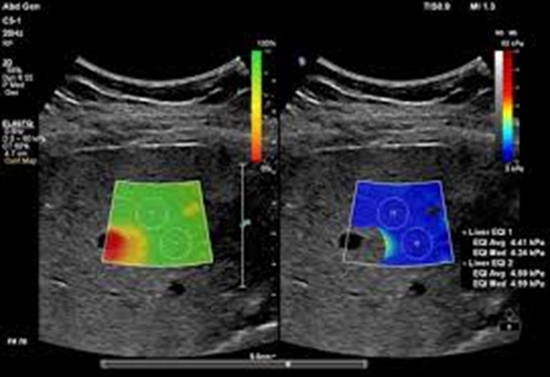

بررسی نقش SWE ) shear wave elastography) در ارزیابی بیماران تحت پیوند کبد و ارتباط یافته های آن با عوارض کوتاه مدت بعد از پیوند کبد در سال های 98 /99 بیمارستان امام خمینی تهران

SWE ) shear wave elastography) در ارزیابی بیماران تحت پیوند کبد و ارتباط یافته های آن با عوارض کوتاه مدت بعد از پیوند کبد